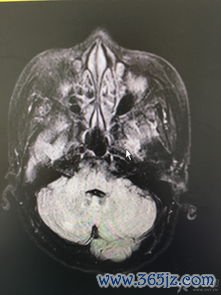

脑转移癌-肺癌脑转移头痛呕吐,放疗科医生说全脑放疗后能缓解

肺癌是常见的恶性肿瘤,其病程中发生脑转移的概率高达20%-65%,这已成为影响患者生存质量与预后的关键因素。脑转移瘤一旦形成,常因占位效应和颅内压升高引发一系列神经系统症状,其中以持续性头痛、恶心呕吐最为常见且令患者痛苦不堪。在自然病程下,若不进行干预,患者的生存期往往非常有限。